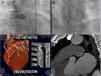

Three patients presented with new-onset crescendo angina reaching III/IV on the Canadian Cardiovascular Society (CCS) angina grading scale, and two had acute coronary syndrome (non-ST elevated myocardial infarction). The coronary angiogram showed CTO of the semi-protected LMCA lesions with two coronary artery bypass grafts previously performed in all patients, one occluded and the other patent (Figure 1). Three patients had saphenous vein grafts to the circumflex coronary artery that were CABG occluded and two patients had left internal mammary artery-left anterior descending artery CABG failure. A coronary CT angiography was performed in one patient to better visualize the CTO (Figure 1).

(A and B) Coronary angiogram showing chronic total occlusion of the left main coronary artery and critical left anterior descending lesion proximal to left internal mammary artery anastomosis; (C) coronary computed tomography angiography showing a short (9 mm), hardly calcified chronic total occlusion lesion: in the middle of the occlusion 100% of the coronary lumen (186 Hounsfield units) was calcified and, in the distal part, 75% of the wall circumference (933 Hounsfield units) was calcified.